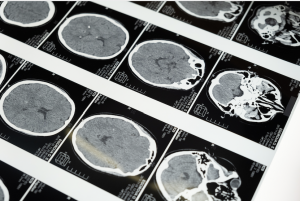

- un scan ou une résonnance magnétique démontrant une atteinte cérébrale aigue (contusion, lésion axonale, hémorragie, œdème, etc.);